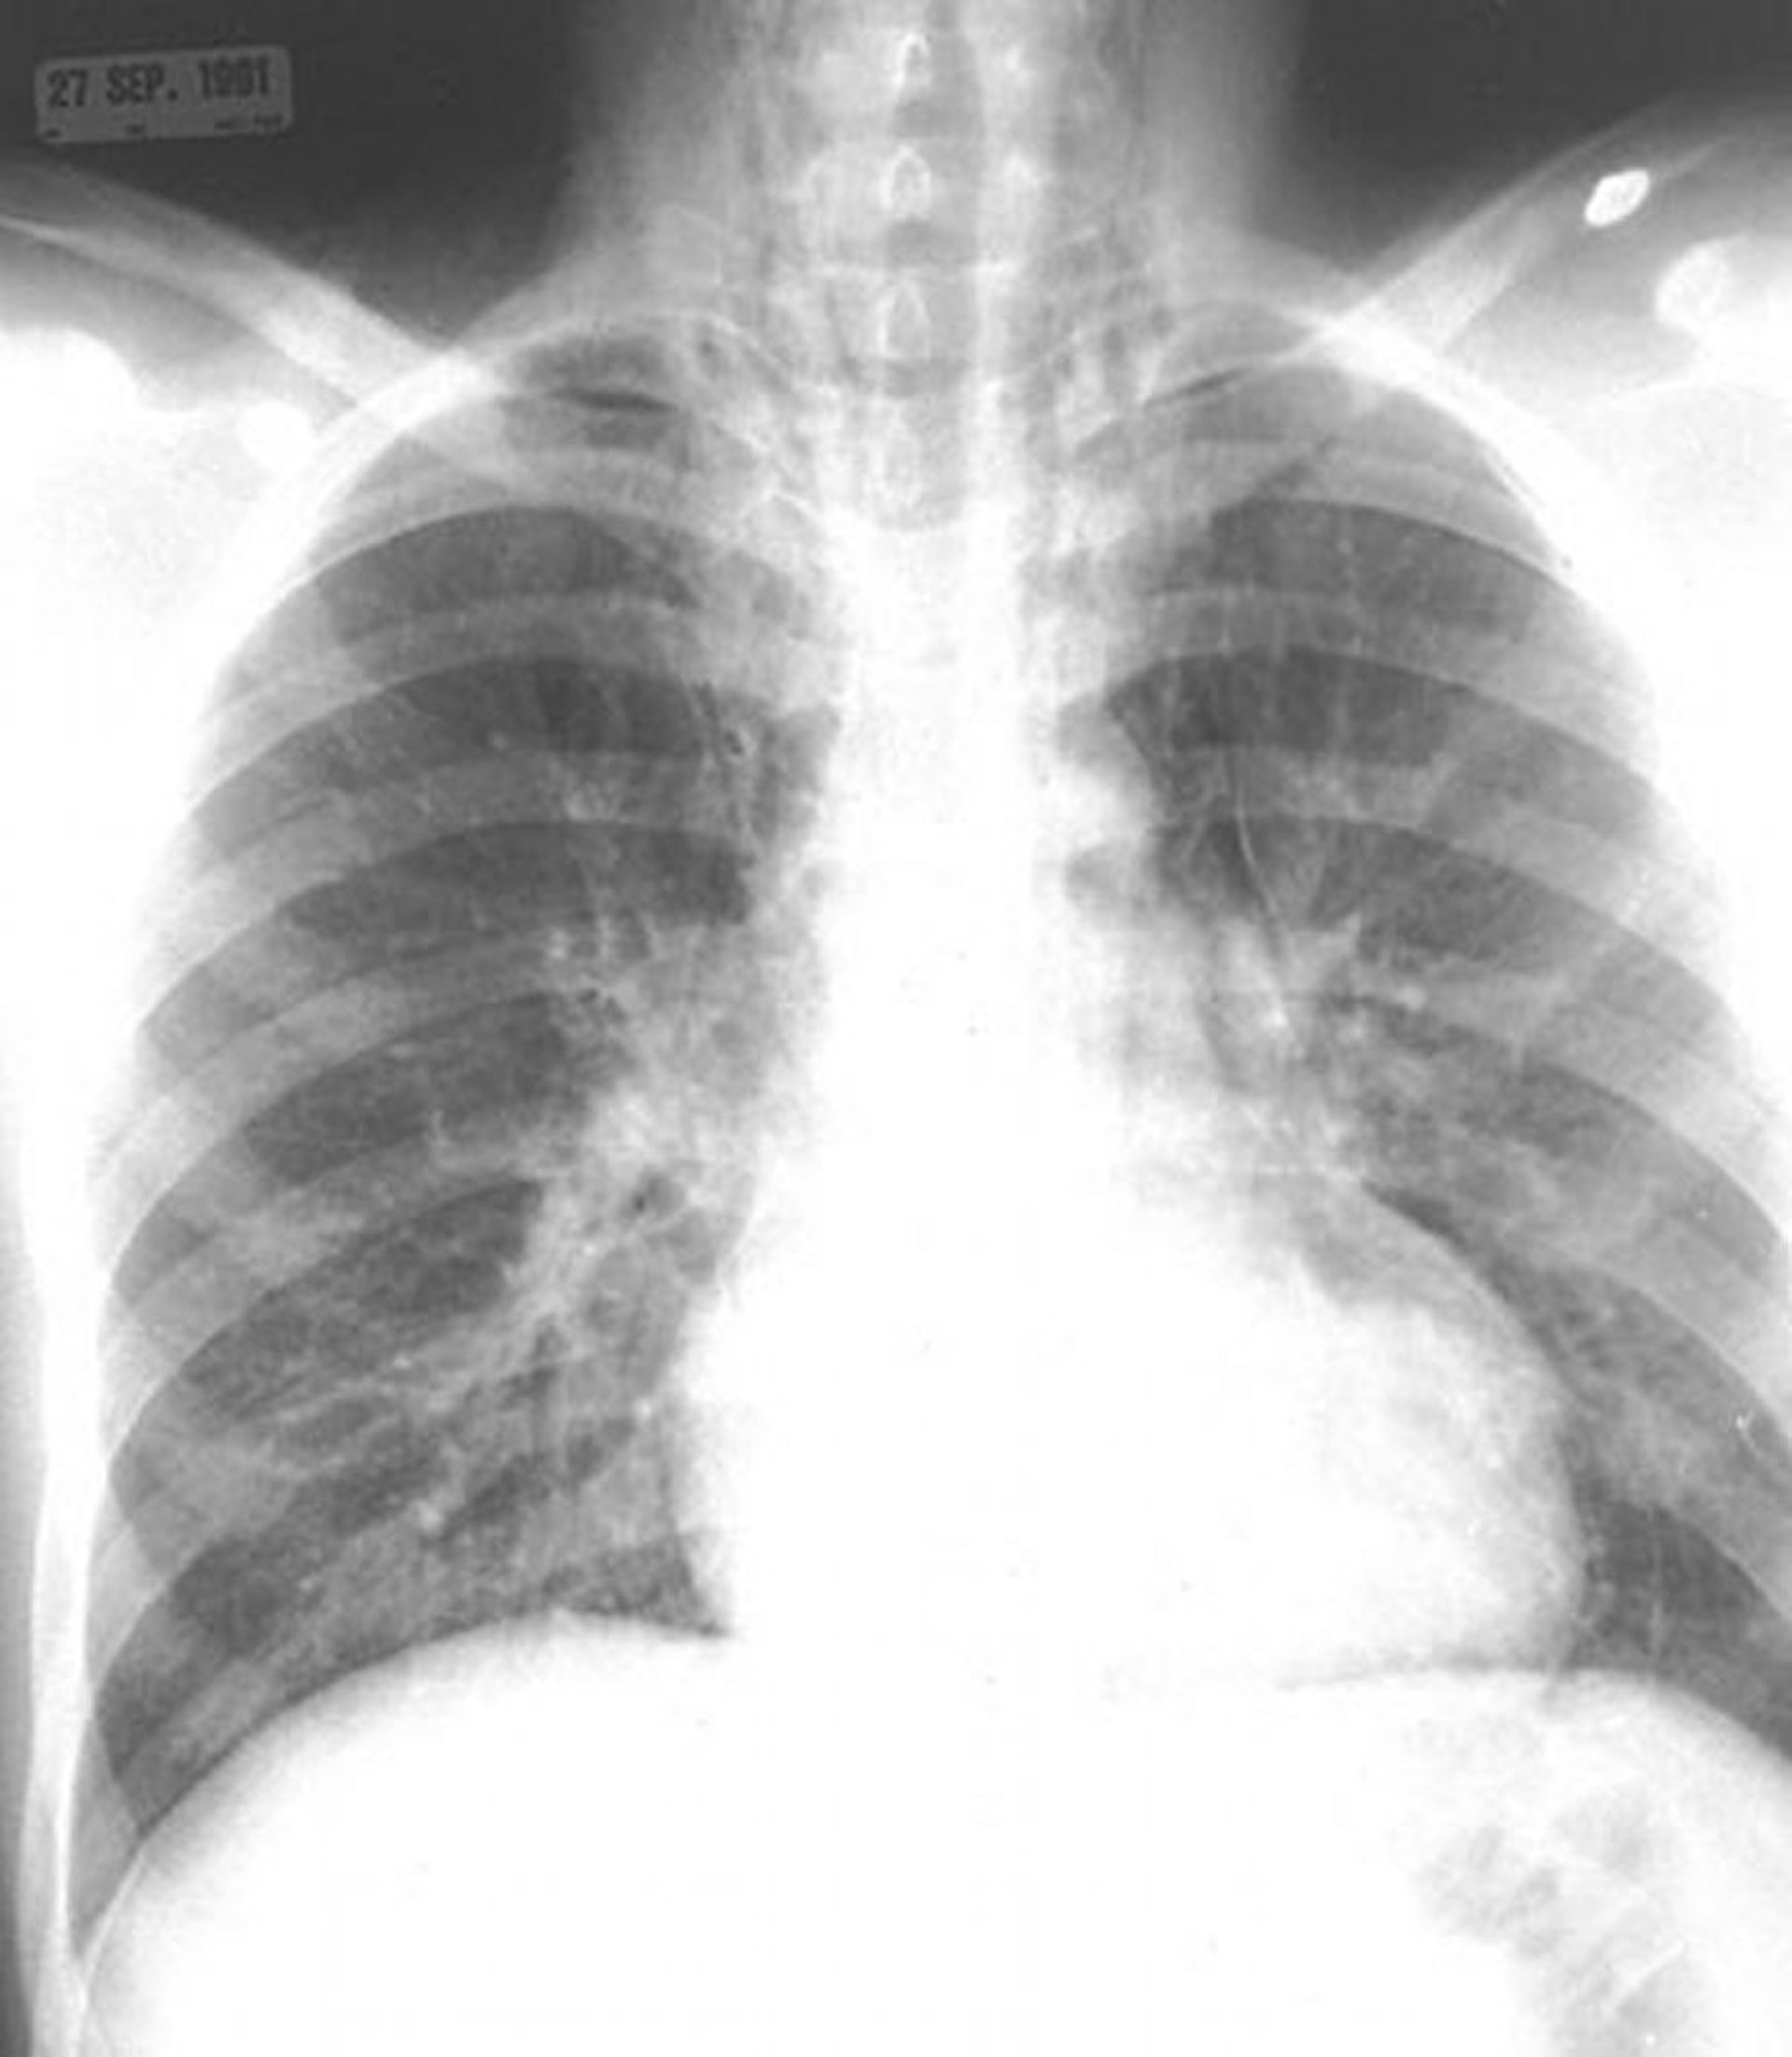

縦隔気腫

縦隔および頸部の軟部組織における空気に注目する。